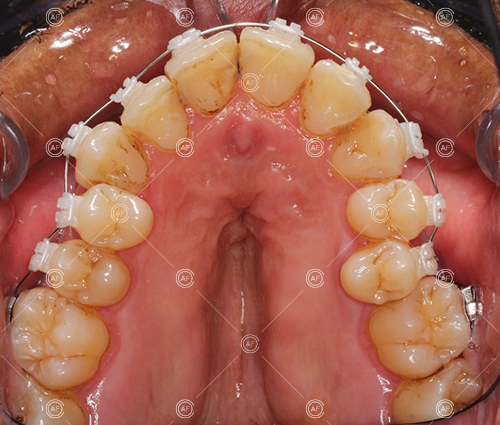

Treatment progressed by starting with thin, flexible nickel titanium archwires of a round diameter, transitioning to a rectangular nickel titanium archwire before eventually working up to a working archwire (1925 stainless steel).

Residual space from the extractions were closed using upper and lower nickel titanium closing coils. Class 2 elastics were used to facilitate space closure in order to gain class 1 buccal segments.